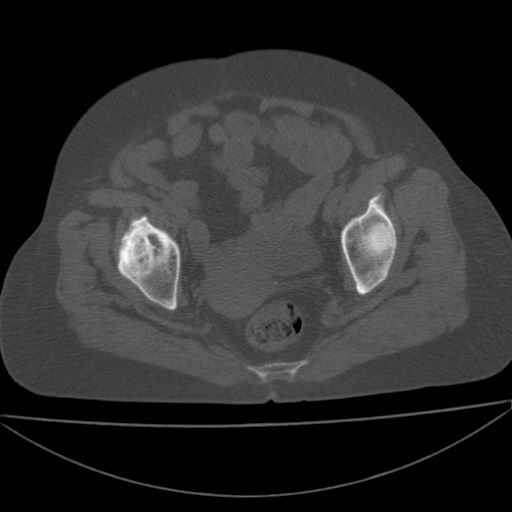

以下是引用余辉在2009-4-23 17:08:00的发言:[br]考虑右髋关节退行性变.股骨颈改变考虑陈旧性骨折可能,股骨头顶部关节面下似有透亮区,股骨头皮质环增厚,考虑有股骨头坏死

以下是引用王显瑞在2009-4-23 16:45:00的发言:[br]考虑股骨颈陈旧性骨折,股骨头缺血型坏死